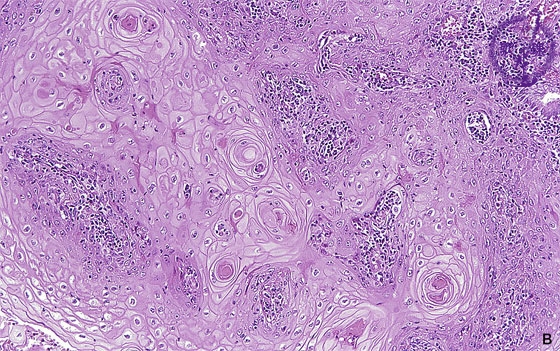

Histology (HE stain, high power): Keratinizing squamous cell carcinoma. Cancer pearls (red dotted line) can be occasionally identified.